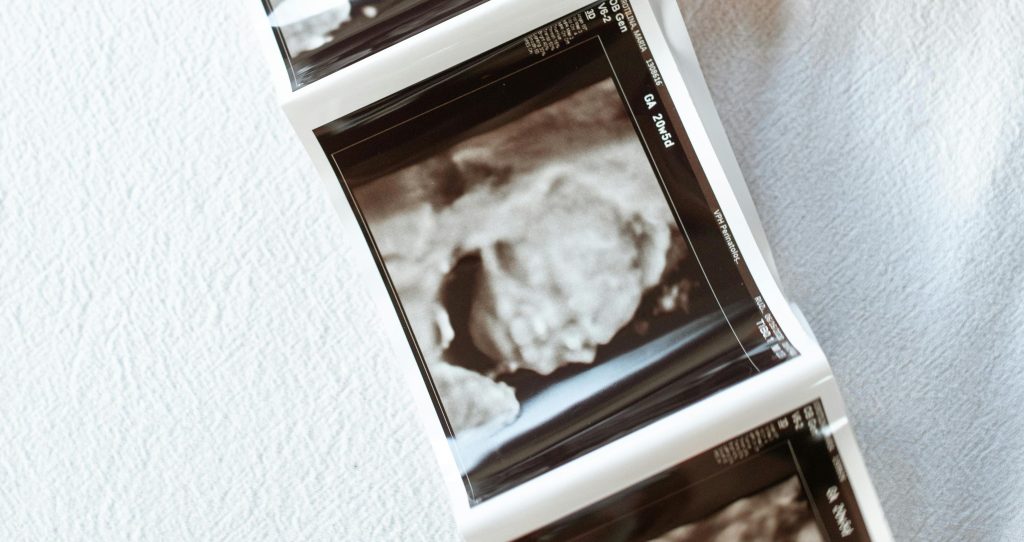

Doar la ecografia 4D sau 3D se poate studia si comunicarea fetala. Spre deosebire de scanarile standard 2D (contururi alb-negru), scanarile 4D arata miscarea in timp real.

Un alt studiu din 2011 s-a concentrat de data asta pe expresiile faciale inainte de nastere, un indicator cheie al raspunsului de plans. Si aici s-a ajuns la o concluzie clara: in timp ce comportamentele non-vocale legate de plans se dezvolta inainte de nastere, componenta vocala a plansului nu incepe decat la nastere. Deci, desi s-ar putea sa vedeti fata bebelusului incordata in timpul trimestrului al treilea la o ecografie, dar nu se va auzi nimic.

In 2005, cercetatorii din Noua Zeelanda au realizat unul dintre cele interesante studii despre plansul bebelusilor in uter, oferind un videoclip cu ultrasunete pe care l-au interpretat ca fiind un bebelus care plangea. Cu instrumente specifice au descompus plansul in mai multe etape, sau o serie de miscari corporale si respiratie (mai degraba decat doar sunet) pentru a confirma daca bebe plangea.